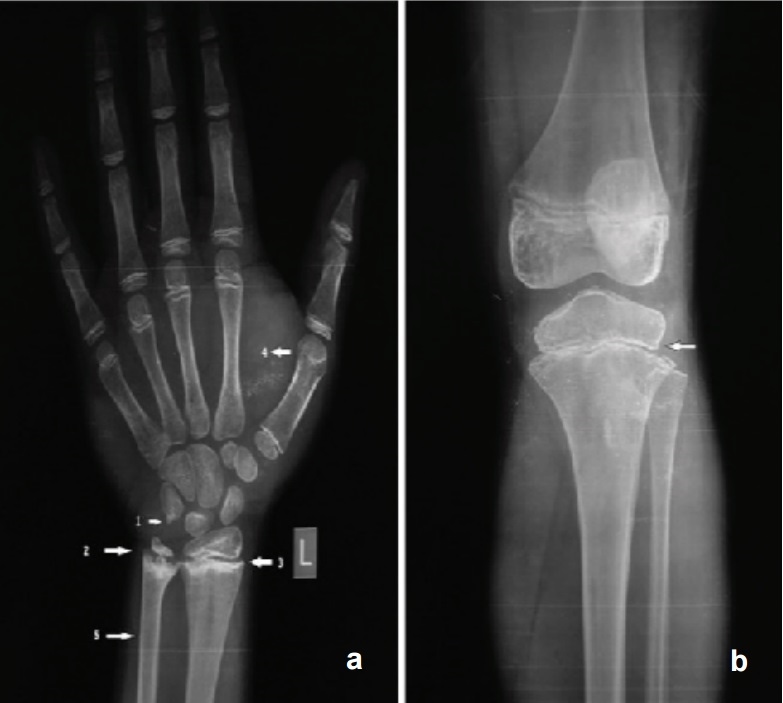

Interestingly, besides delayed bone age, characteristic x-rays were noted in about 75% of the hypothyroid patients (Figure 4).

Click here to download Figure 4Figure 4a. X ray wrist showing bone age of 10 years (chronological age 16 years) 1. Epiphysis of pisiform just appearing 2. Irregular ossification of growth plate 3. Sclerotic band at radial metaphysis 4. Soft tissue thickening 5. Pencil thin cortex; Figure 4b. X ray of the knee showing heterogeneous epiphysis with irregular ossification of growth plate.